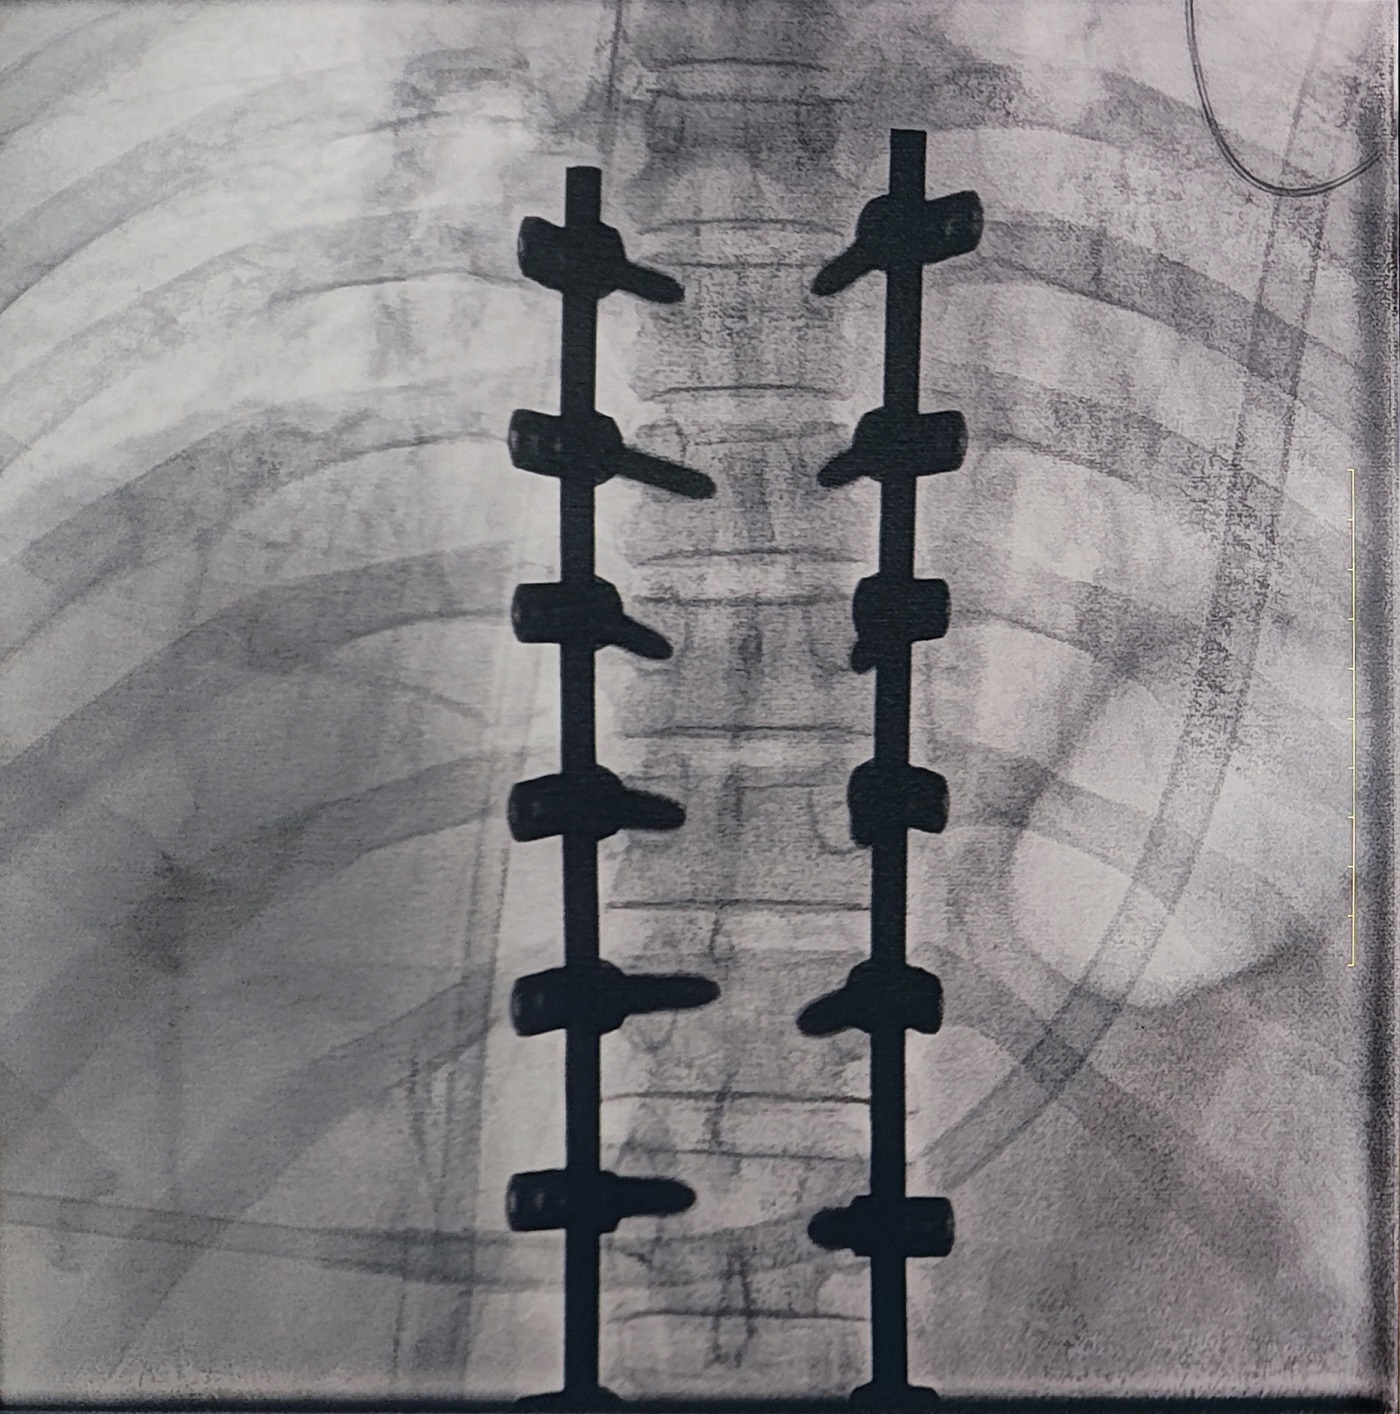

一場(chǎng)脊柱手術(shù)中,醫生需要拍攝跨越7個(gè)節段的脊柱影像,由于曝光的視野較大,常規視野的C形臂通常需要拍攝2-3次,普愛(ài)醫療大平板一體式C形臂30CM*30CM的“大視野”,輔助醫生一次性完成了7個(gè)節段的拍攝。最終,醫生在高清影像的輔助下完成了14枚螺釘的精準定位、置入。

大視野,不僅意味著(zhù)醫生可以更快,獲取更全面的影像信息,做出精準判斷,無(wú)需多次拍攝定位,也顯著(zhù)地降低了患者接受的輻射劑量。